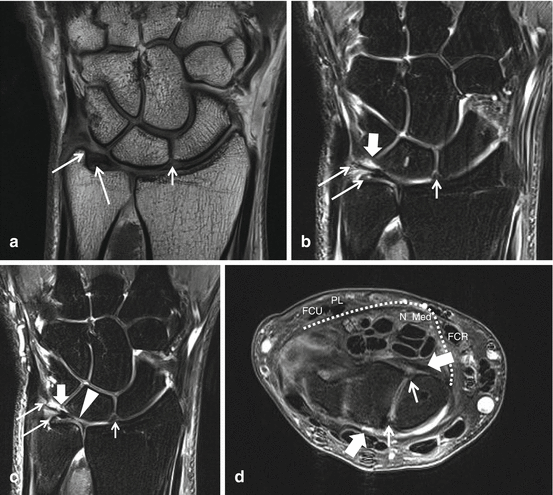

Магнитно-резонансная томография (МРТ)

Это высокоточный метод визуализации, позволяющий получить детальное представление о состоянии мягких тканей запястья, таких как связки, сухожилия, мышцы, нервы и кровеносные сосуды. В отличие от рентгенографии, МРТ не использует ионизирующее излучение, что делает ее более безопасной для пациента. В контексте диагностики туннельного синдрома карпального канала МРТ дает возможность визуализировать срединный нерв на всем его протяжении в области запястья, оценить его форму, толщину и наличие признаков сдавления. Кроме того, МРТ позволяет выявить возможные причины компрессии нерва, такие как утолщение связки, воспаление сухожилий или наличие аномальных образований (например, гигромы).

Процедура МРТ запястья обычно не занимает много времени. Пациента помещают в туннель томографа, где он должен сохранять неподвижность в течение нескольких минут, пока аппарат сканирует область запястья. Для получения более четких изображений может быть использовано внутривенное контрастирование, которое позволяет лучше визуализировать кровеносные сосуды и воспалительные изменения.

В некоторых случаях, например, при подозрении на перелом кости или наличие металлических имплантов, которые являются противопоказанием к МРТ, может быть назначена компьютерная томография (КТ). КТ также является информативным методом диагностики, но он основан на использовании рентгеновского излучения.